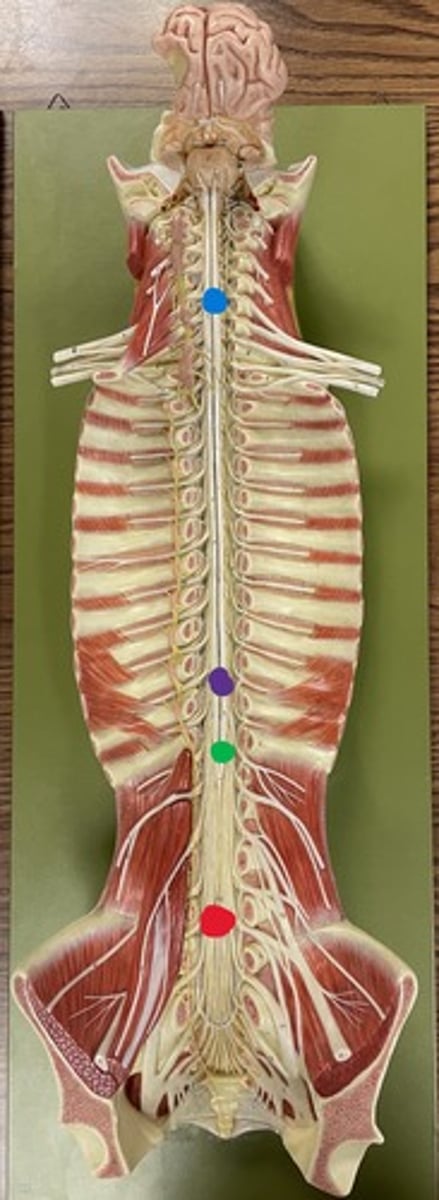

Cervical enlargement

Blue

Lumbar enlargement

Purple

Conus medullaris

Green

Cauda equina

Red

Filum terminale

blue